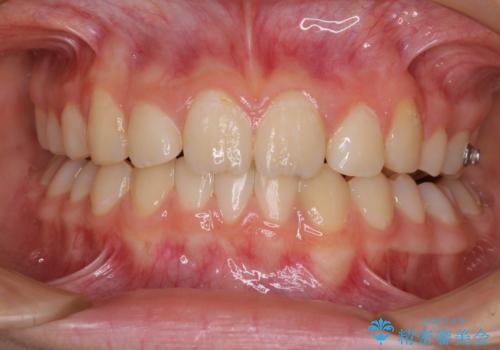

目立つ八重歯を治したい インビザラインによる矯正治療

- 目立つ八重歯を改善したいとのことで来院された患者様です。

奥歯の咬み合わせは左右とも理想的なものでしたが、下顎前歯が1本欠損しているため、上下のバランスを保つことが難しい歯列でした。

唇を閉じたときに上顎前歯が下顎の唇に乗っかる印象があったため、八重歯の後方にある小臼歯を1本抜歯することとしました。

変則的な抜歯となるため、臼歯の咬合が理想的でなくなることが懸念されますが、インビザラインにて矯正治療を行うこととしました。